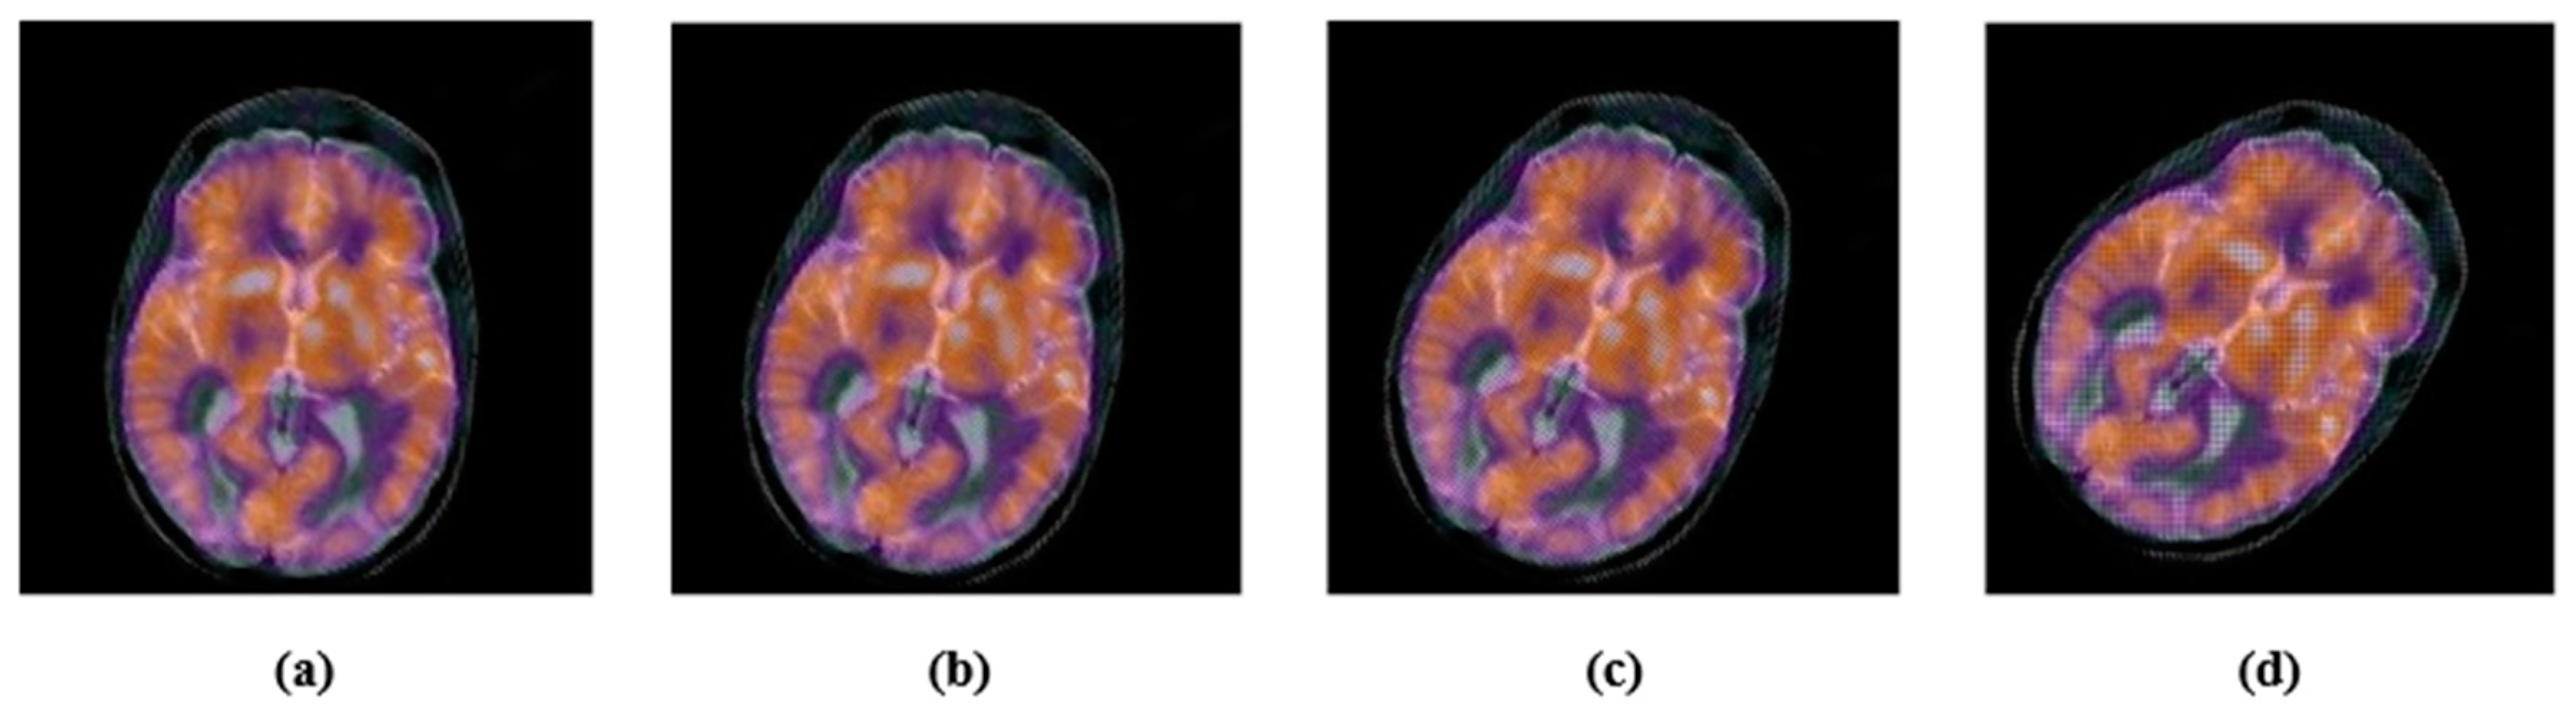

4.2. Robustness

4.2.1. Common Signal Processing Attacks

4.2.2. Geometric Attacks